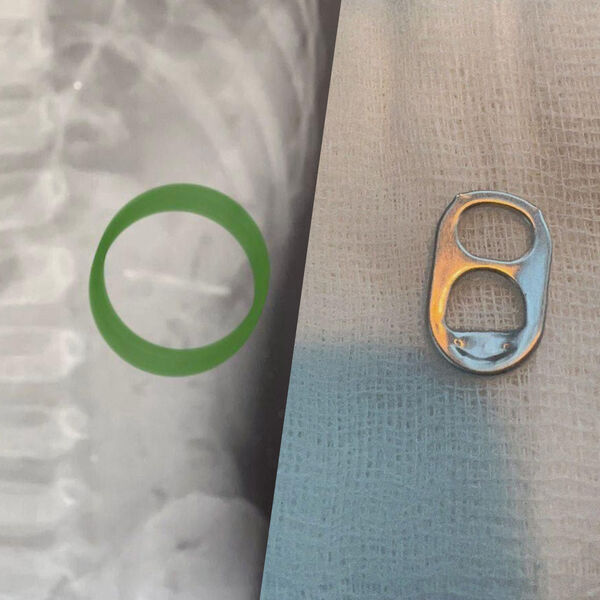

Врачи Раменской больницы спасли полуторагодовалого ребенка, который проглотил ключ от металлической банки. Об этом сообщили в пресс-службе минздрава Московской области.

Мальчика в больницу привезли родители. Они рассказали, что сын играл с маленькой деталью и по неосторожности проглотил ее. Обследование показало, что ключ от банки находится в желудке.

«Слизистые оболочки внутренних органов были не повреждены. При помощи эндоскопического инструмента металлический предмет с острыми краями был аккуратно извлечен», — рассказал заведующий детским хирургическим отделением больницы Владимир Хабалов.